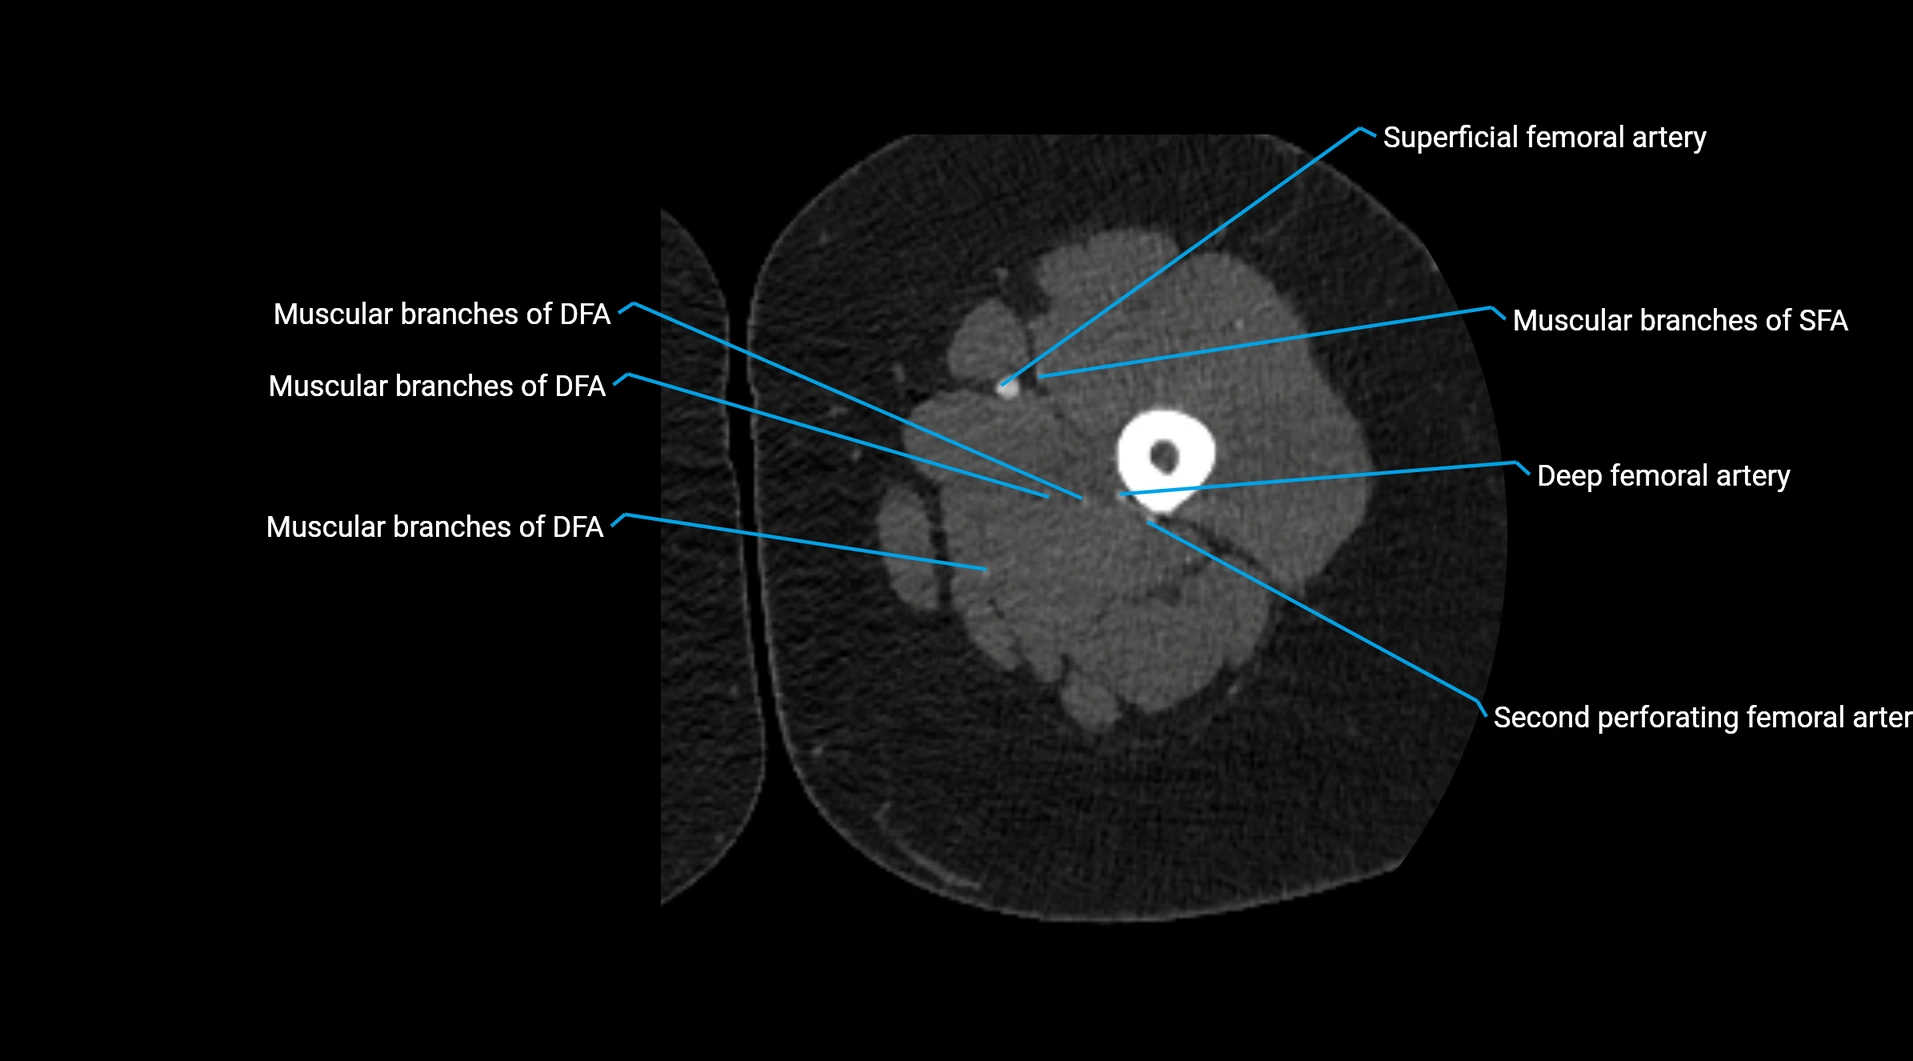

CT Appearance

Non-contrast CT:

• Appears as a tubular soft tissue structure anterior to vertebral bodies

• Calcified atherosclerotic plaques appear as hyperdense foci along the wall

• Useful for screening abdominal aortic aneurysm (AAA) size and mural calcification

Contrast-enhanced CT (CTA):

• Gold standard for abdominal aortic imaging

• Provides excellent detail of lumen, wall, aneurysm, thrombus, and branch vessels

• Multiplanar and 3D reconstructions help in aneurysm measurement, stent graft planning, and dissection evaluation

• Detects acute rupture, traumatic injury, or occlusion with high sensitivity